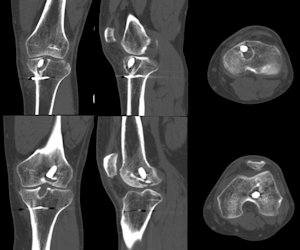

Çoğu durumda tek bir cerrahi işlem ile revizyon ön çapraz bağ cerrahisi yapılabilir, ancak nadir de olsa iki aşamalı revizyon gerekli olabilir. Birden fazla cerrahi gereken durumlar aşağıdaki gibidir;- İlk cerrahi sırasında açılan tünellerde ileri derecede genişleme var ve revizyon sırasında yeni bağın tespiti mümkün değilse iki aşamalı cerrahi yapılabilir. Önce tüneller, vücudun başka bir bölgesinden alınan kemik parçaları ile doldurulur ve iyileşmesi beklenir. Altı ay sonra yeterli kemik oluştuktan sonra revizyon yapılır (Resim 4)

Resim 4: İlk cerrahi sonrası tünel genişlemesi saptanan hastaya ait görüntüler.